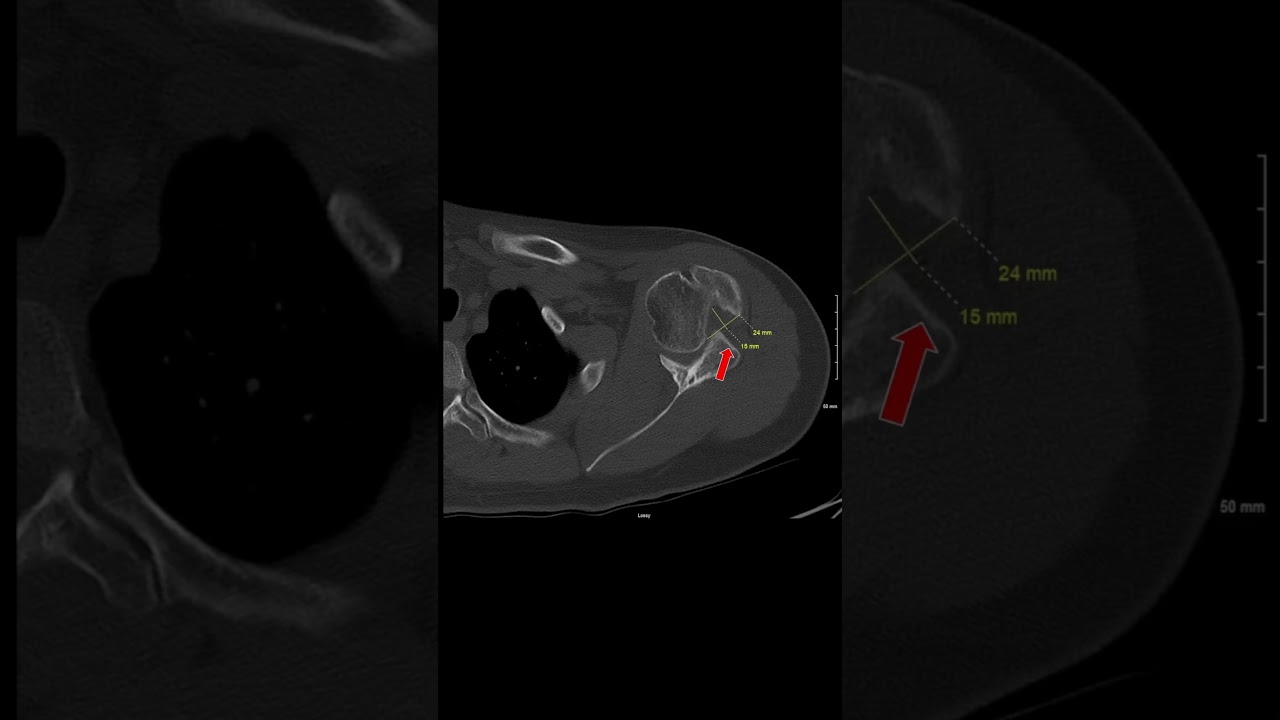

CT of Chronic Shoulder Dislocation

This is the CT of a patient with a chronic shoulder dislocation....